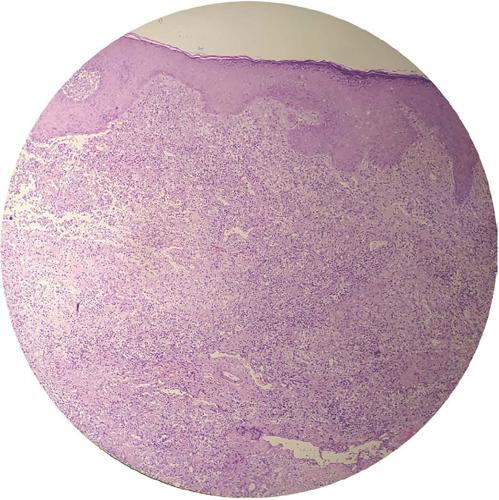

Foi realizada biópsia da lesão cutânea com exame anatomopatológico, que evidenciou um infiltrado inflamatório misto, com ectasia vascular, hemorragia e acúmulos de histiócitos, esboçando granulomas malformados (Figura 2). Parte do material também foi enviado para cultura, sem crescimento de micobactérias.